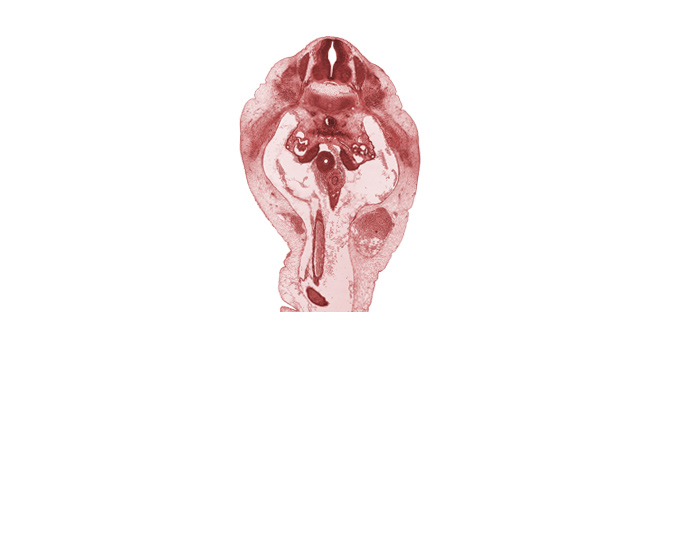

Carnegie Embryo #6520 | Location: 23-02-05

Keywords: T-12 spinal ganglion, T-12 spinal nerve, blastemata of abdominal wall muscles, duodenum, edge of herniated midgut mesenchyme, epimere, gonadal ridge, mesonephric glomerulus, superior mesenteric artery, superior mesenteric vein

Source: The Virtual Human Embryo.